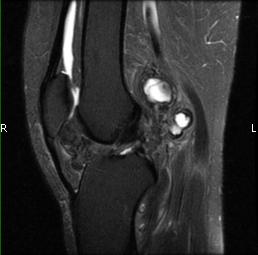

MRI (Fig. 1-10)

- Periarticular or synovial nodular mass with varying degrees of bone erosion.

- Nodular lesion with areas of hemosiderin (low signal on all sequences) and hemorrhage.

- On fat suppress images the tumor is high signal and hemosiderine cannot be seen.

- Joint effusions and bony erosions are well demonstrated. As with CT, contrast enhancement is typical.

Fig. 1-10: Magnetic Resonance of a PVNS of the knee shows a synovial mass with minimal bone erosion of the medial articular plate. On T1W and T2W images shows a tumor with low intensity areas (hemosiderin) and hemorrhage. Joint effusion is well demonstrated. Post contrast images demonstrate an irregular pattern of enhancement.